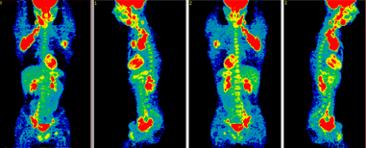

• Use low doses of radioactive substances or compounds that attach to tumor cells.

• Traced in the body to see where and when they concentrate.

• PET scans play a role in determining whether a mass is cancerous, reoccurring or to check if a treatment is working.

• Not recommended for screening, but can be used as follow up to screenings

• Cost $1000-$8000